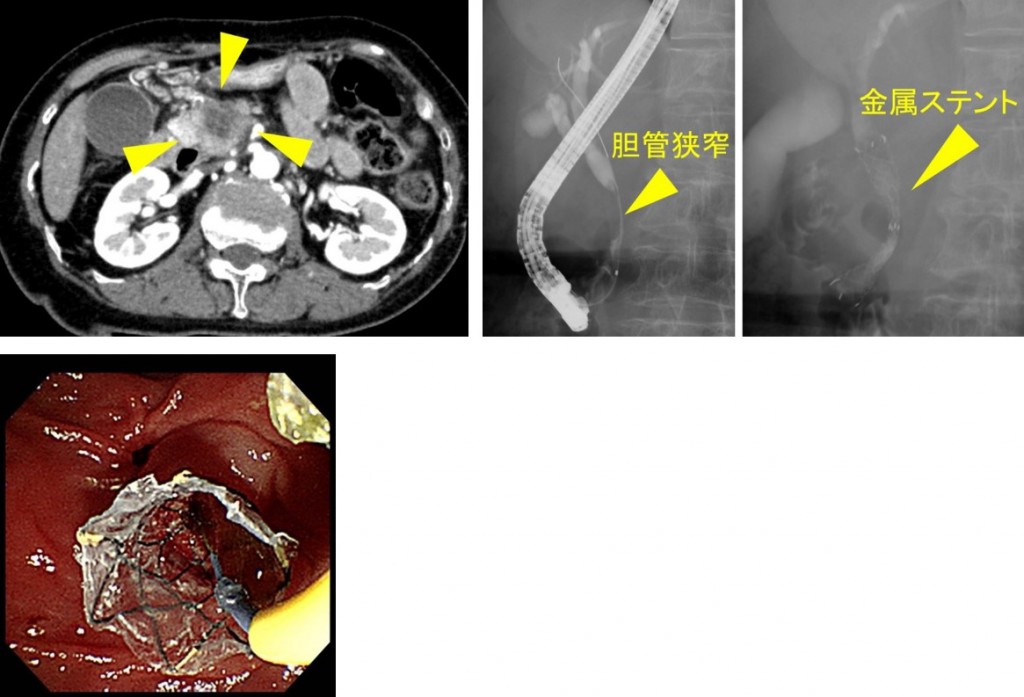

内視鏡的逆行性胆管膵管造影 (ERCP) および磁気共鳴胆管膵管造影 (MRCP) は医療検査です。以下のような胆管や膵管の問題を診断するために使用されます。

ERCP では、内視鏡と X 線を使用して管の画像を作成します。これは、胆汁および膵臓の問題を診断するための標準的な方法です。しかし、それは侵襲的であり、さまざまな合併症を伴います。

ERCP を使用すると、医師は次のような特定の治療を完了することもできます。

- 括約筋切開術

- ステント留置

- 石の除去

ERCP を取得できない場合は、MRCP を代替として使用できます。 MRCP は、術前処置として ERCP が必要かどうかも判断できます。